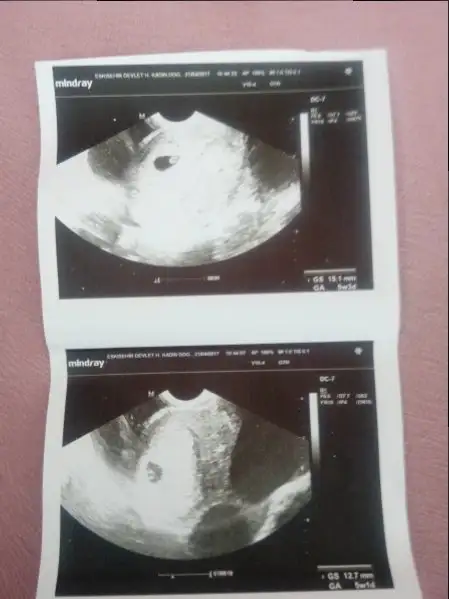

Canım korkma bir şey olmamıştır ama neden vajinal ultrason? Mümkün olmadıkça baktırmamak lazım bencede. Dikkat et kendine bol bol dinlenmeye çalış benceBende bugün 6+3 oldum..Sabah doktora gittim vajinal ultrasondan baktı ve kalp atışını duydum çok şükür ama muayeneden kalkar kalkmaz kahverengi kanamam oldu..Sevinemedim bile kalp atışlarınaMecbur kalmadıkca vajinal ultrason yaptırmam bir daha..Dua edin arkadaşlar birşey olmamıştır inşallah bebeğime